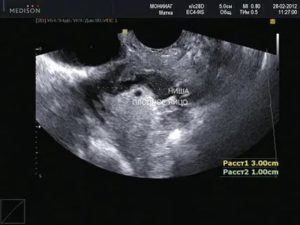

На 10-14 неделе беременности женщина проходит ультразвуковое исследование, позволяющее врачу сделать замеры плодного яйца для установления точного срока гестации. Иногда в ходе обследования обнаруживается деформированное плодное яйцо. Основной причиной этой патологии считается повышение тонуса матки.

При нормальном наступлении беременности околоплодное яйцо располагается в матке. На маленьком сроке, в 5-6 недель оно становится округлым или каплевидным. К 6-7 неделям на продольном скане УЗИ яйцо выглядит овальным, а на поперечном сохраняет округлость. Если же обследование показывает приплюснутость плодного яйца по бокам и отсутствие овальной формы, значит матка находится в тонусе.

Чем может грозить изменение форм и размеров околоплодного яйца? Сильное превышение или уменьшение его размеров свидетельствует о замирании беременности, но, как правило, врач продолжает наблюдения, контролируя динамику развития изменений. О замершей беременности говорит и вытянутое плодное яйцо.

При увеличении тонуса матки углы оболочки яйца выглядят неровными. В большинстве случаев врачи считают такие изменения безобидными, если только они не сопровождаются раскрытием шейки, темными выделениями и болями. При подобных симптомах появляется реальная угроза потери плода.

Низкое положение плодного яйца в полости матки требует постоянного контроля. Если оно очень близко подходит к шейке матки, врач может принять решение о его удалении. При внематочной беременности УЗИ показывает, что плодное яйцо не содержит эмбриона, вместо него в полости яйца присутствуют жидкость и сгустки крови.